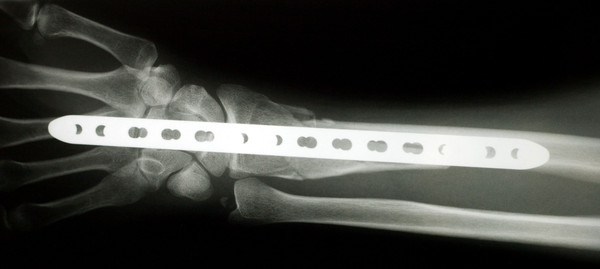

On september 16 of 2007, I took a ride on my 1982 yamaha seca 400 … I had just synced the carbs and the bike was runnin good… so good.. it caught me by surprise. As I went through an s turn, the bike accelerated better than expected. It was dark and my headlight was angled too low, which gave me little time to see the back side of the s-curve. I hit the brakes and skidded into the curb which dumped me into the grassy median. I would guess I was going 35 mph when I hit. As I fell, my left hand instinctively tried to catch my fall. Bad idea, because I heard my forearm shatter like a tree branch snapping, then I rolled 1 time onto my right shoulder (fracturing it). I’ve been riding since 82 and this is my first accident.